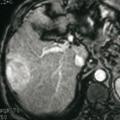

Carcinome hépatocellulaire

TUMEURS DU FOIE

CARCINOME HEPATOCELLULAIRE

Image typique de CHC